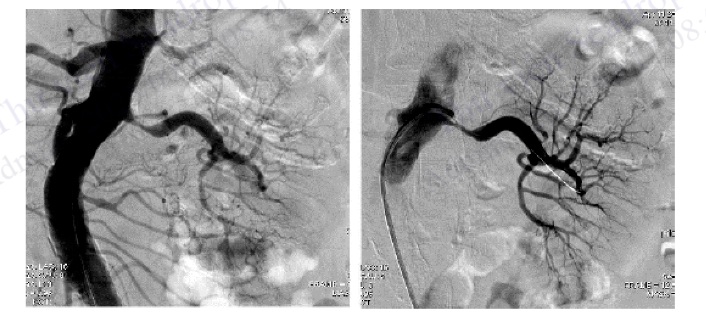

Hình 4.93. Chụp ĐMV trái ở tư thế nghiêng phải chếch chân đánh giá ĐM mũ và đoạn gần ĐM liên thất trước

Hình 4.94. Chụp ĐMV phải ở tư thế nghiêng trái (LAO 30)